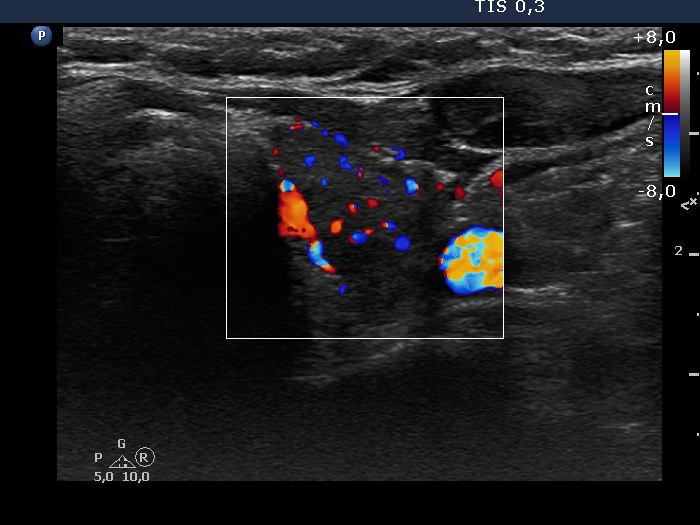

Consecutive patients with the final diagnosis of Hashimoto's thyroiditis - case 34 (927) (ultrasonographic picture 6)

Right lobe, longitudinal scan

Left lobe, transverse view, color Doppler mode. The vascularization is increased.